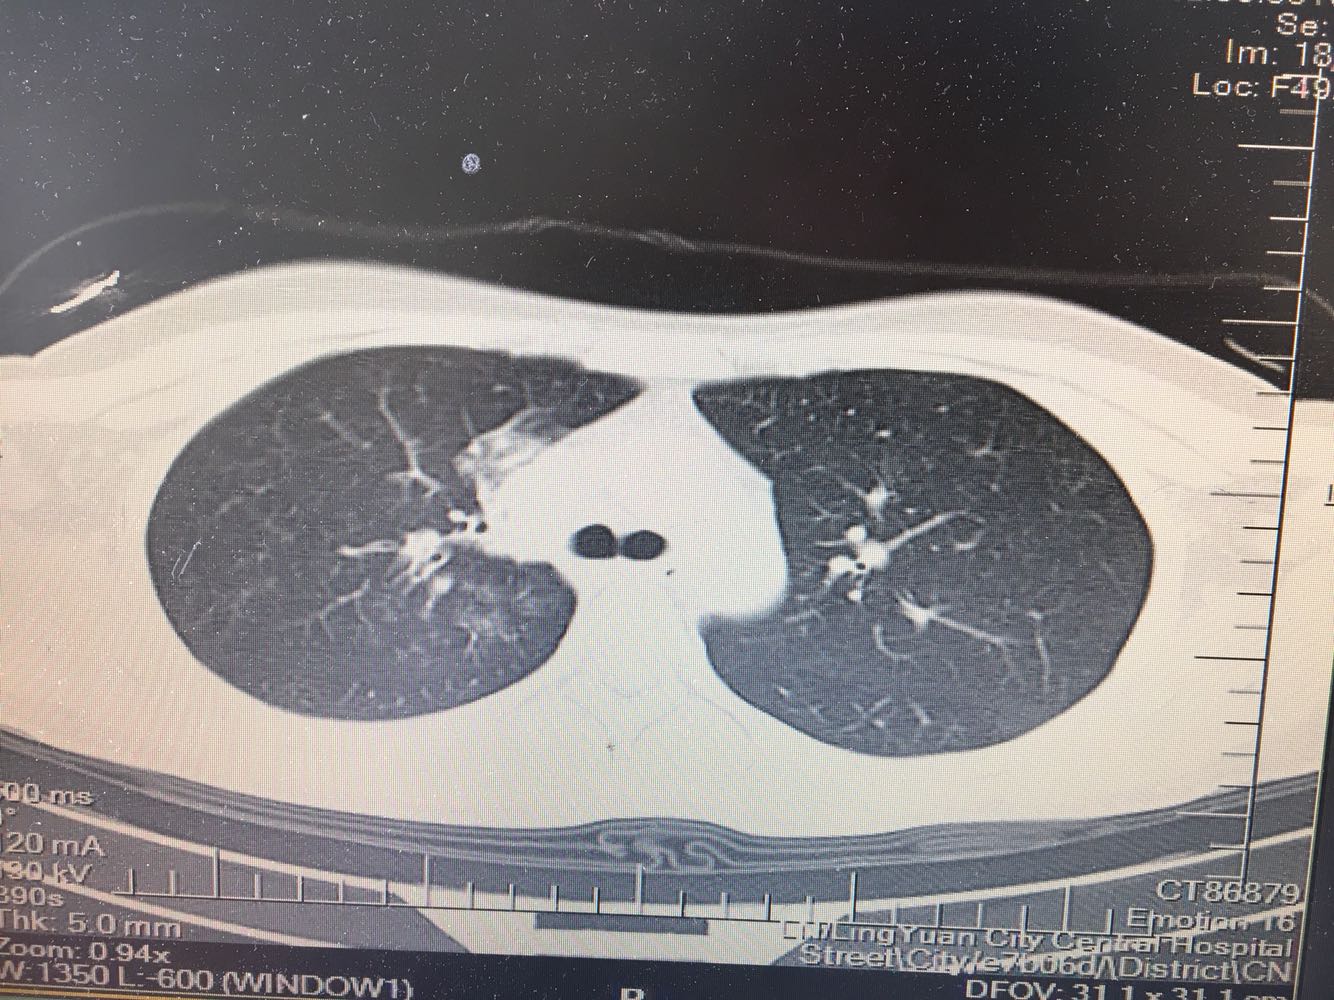

支原体肺炎?肺结核?

女,26岁,咳嗽1周,咳痰不畅,咽喉痒,口服阿莫西林无好转,昨日发热,体温38.5摄氏度,于门诊查肺CT后以肺炎收入院,病来无盗汗,无咳血,无消瘦及乏力,无头痛,无肢体酸痛,饮食睡眠可,二便正常

支原体抗体1:160,结核抗体弱阳性。支原体肺炎个别可见上叶病变,该患无结核中毒症状,考虑支原体肺炎可能性大,但肺尖为结核好发部位,需要抗炎治疗后复查观察疗效。